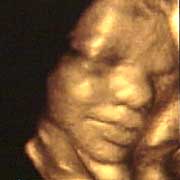

圖文:胎兒子宮內(nèi)表情豐富 專家稱提供研究新依據(jù)

中新網(wǎng)9月13日電 英國(guó)天空新聞報(bào)道,英國(guó)科學(xué)家圖亞特·坎貝爾最近利用先進(jìn)的掃描技術(shù)清晰地拍下了孕婦子宮中胎兒的表情,透過(guò)他拍攝的照片,人們可以清楚的看到一個(gè)尚未降臨世間的小生命喜、怒、哀、樂(lè)的表情。

斯圖亞特.坎貝爾是倫敦著名的產(chǎn)科教授,他利用超聲掃描技術(shù)拍攝到了胎兒在子宮中打呵欠、眨眼、吮手指、哭泣甚至微笑的畫(huà)面,這些都為胎兒行為的研究提供了新的依據(jù),專家認(rèn)為,這一突破將推動(dòng)?jì)雰航】悼茖W(xué)的發(fā)展,包括對(duì)唐氏綜合癥等嬰幼兒疾病的診治將起到極大的推動(dòng)作用。

此前,醫(yī)學(xué)界一直認(rèn)為,嬰兒要到降生后才可以做出喜、怒、哀、樂(lè)的表情,要通過(guò)模仿母親才可以學(xué)會(huì)微笑。

坎貝爾教授說(shuō):“有個(gè)這種技術(shù),現(xiàn)在許多問(wèn)題都可以進(jìn)行研究了。比如說(shuō),患有唐氏綜合癥的嬰兒和正常嬰兒的活動(dòng)方式是否一樣?胎兒是否因?yàn)楦吲d才笑?胎兒哭是否是因?yàn)樵谧訉m中受到打擾?既然我們都認(rèn)為子宮內(nèi)是一片黑暗,那胎兒為什么會(huì)眨眼呢?”(章田)